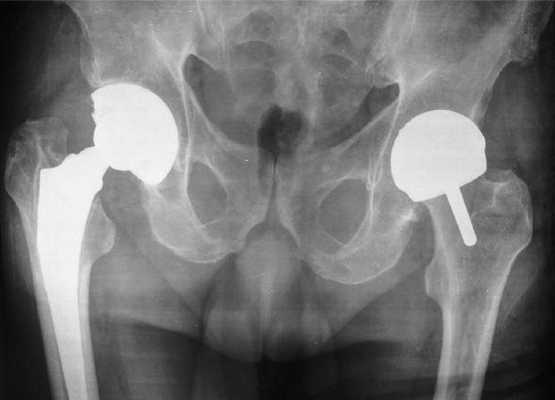

Тотальная и поверхностная операция на рентгене.

Головка бедра при коксартрозе.